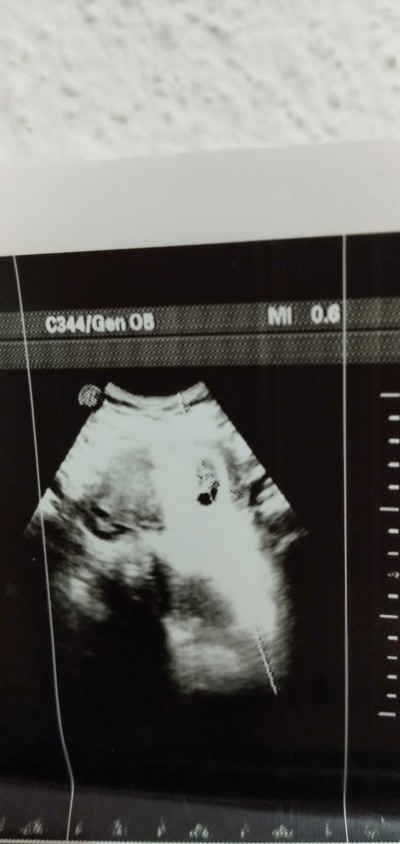

Merhaba arkadaşlar çok erken biliyorum ama belki keseden tahmin yürütecek arkadaşlar var cinsiyet tahmini alabilir miyim... Ekşi tuzlu çok aseriyorum bulantılarım yok denecek kadar az çok bel ağrısı çekiyorum özellikle sol tarafında.. 8+3 yorumlarınızı bekliyrm

Gebelik haftası 8+3